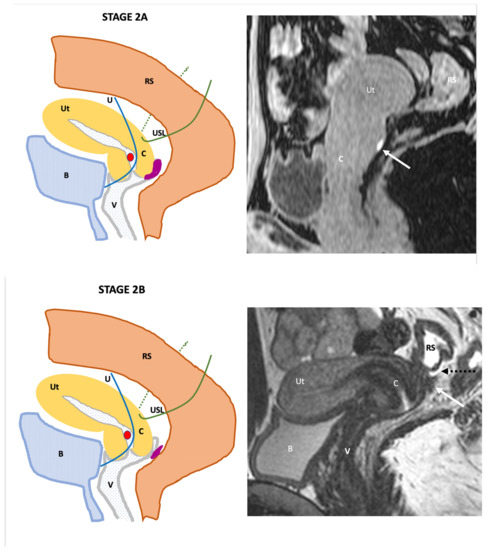

| Endo-Stage MRI | Location | Extent | Risk Stratification |

|---|---|---|---|

| Endo-Stage MRI 0 | Superficial endometriosis |

| Low |

| Endometriosis is strictly confined to the ovaries |

| ||

| Endo-Stage MRI I | Endometriosis is strictly confined to the retrocervical area |

| |

| Endo-Stage MRI II | Endometriosis invades beyond the retrocervical area, but not to the pelvic side-wall |

| Endo-Stage MRI III | Endometriosis extends to the pelvic side-wall and/or causes hydronephrosis or non-functioning kidney |

| Intermediate |

| Endo-Stage MRI IV | Endometriosis has involved the bladder or rectosigmoid colon |

| Endo-Stage MRI V | Multiple deep endometrioticlocations |

| High |